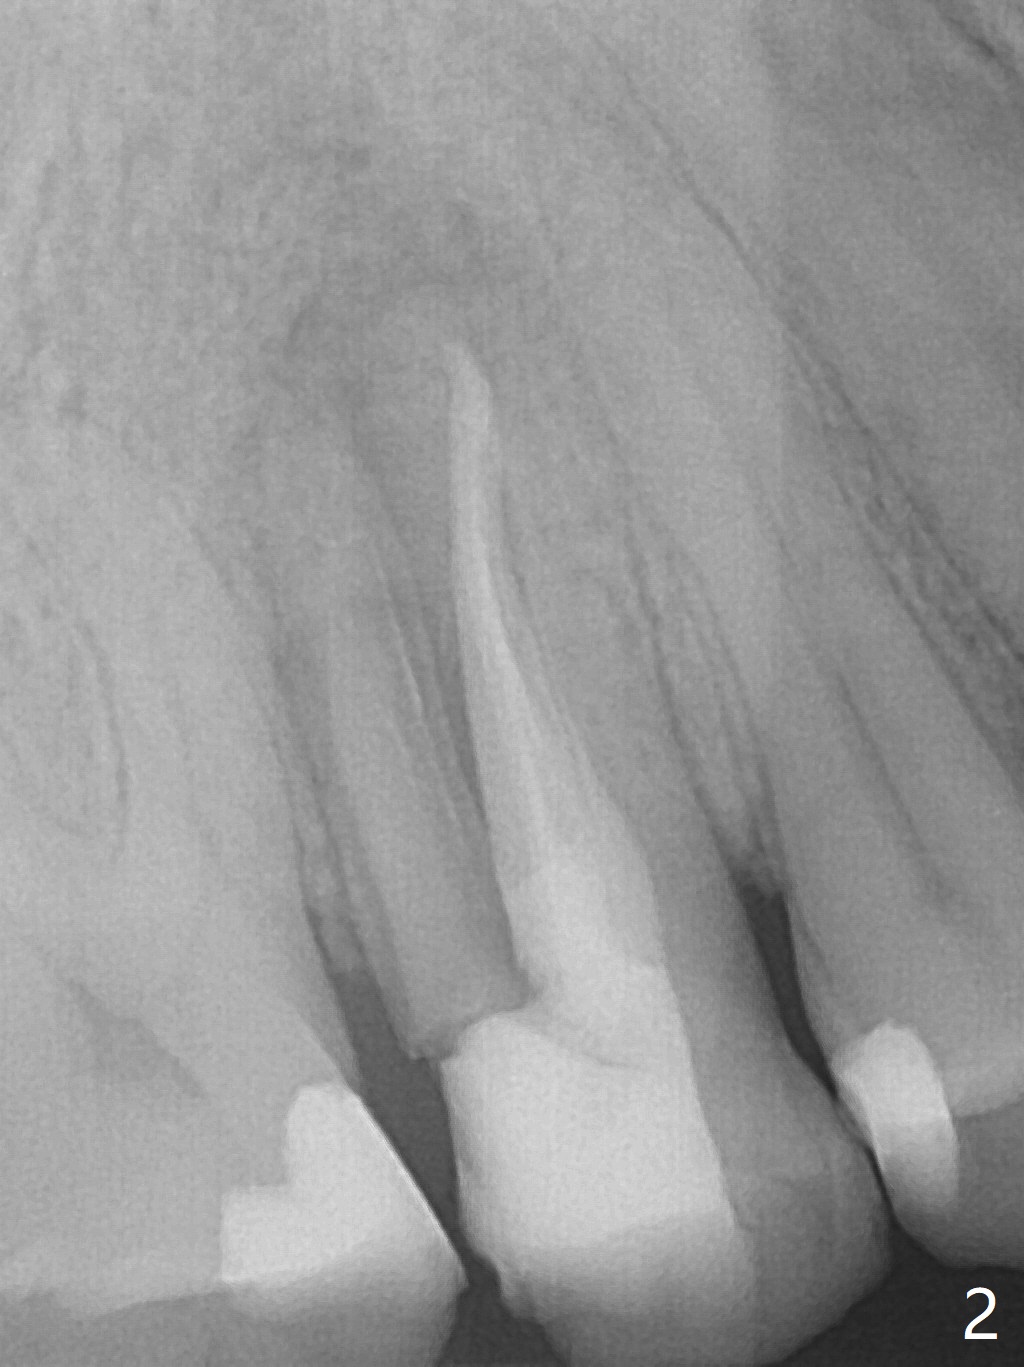

Nine months post apicoectomy of the tooth #4 of a 40-year-old man (Fig.1 <), the root has vertical fracture (Fig.2). It appears that the patient is a bruxer. Place an implant as long as 18 mm (bone level, Fig.3). Start osteotomy in the middle of socket, since there is bone resorption both buccally (apicoectomy) and palately (Fig.4 *). The implant should occupy the meisodistal space for primary stability. Measure root dimension post extraction to determine the implant diameter. Use a 3.8 mm dummy implant.